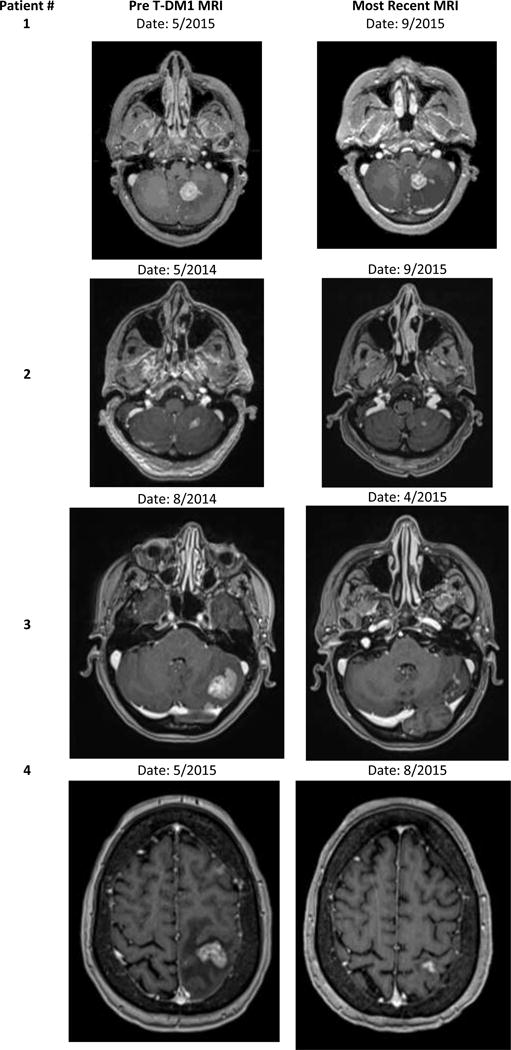

Figure 1.

Representative images of intracranial response to TDM1 among four patients treated at the University of North Carolina at Chapel Hill

In July of 2014, an enlarging and symptomatic intracranial lesion in the frontal lobe was surgically resected; pathology revealed radiation necrosis. SRS was subsequently performed on 3 progressive intracranial lesions in October 2014. A restaging brain magnetic resonance imaging (MRI) showed progression in 2 intracranial lesions, prompting initiation of vinorelbine/everolimus/trastuzumab on a clinical trial which was discontinued after 5 cycles again due to intracranial disease progression. T-DM1 was initiated and after 4 cycles, a brain MRI illustrated a measurable reduction in the size of several intra-cranial lesions (Figure 1, Patient 1). The largest lesion, a 22 mm enhancing lesion in the corpus callosum, decreased to 14 mm. A 22 mm lesion in the left cerebellar hemisphere decreased to 17 mm. The patient’s neurologic status was stable and steroids were no longer required to maintain symptom control.

In April 2013 headaches prompted a brain MRI; multiple brain metastases throughout both the cerebellum and left cerebral hemispheres were discovered. She received whole-brain radiation therapy (WBRT) to a total dose of 35 Gy in April 2013. Systemic therapy was restarted with nab-paclitaxel, trastuzumab, and lapatinib in June 2013 through January 2014 when intracranial disease progression prompted SRS therapy to a single cerebellar lesion at a total dose of 25 Gy. Then patient then transitioned to vinorelbine, everolimus, trastuzumab on a clinical trial in March 2014 which was discontinued due to intracranial progression in May 2014. She initiated TDM1 and has remained clinically stable on treatment for over 16 months with measurable reduction in the size of numerous intracranial lesions as per brain MRI September 2015 (Figure 1, Patient 2).

Letrozole/trastuzumab with zolendronic acid stabilized was continued until disease progression in August 2014 at which time pulmonary nodules and 2 new brain metastases were found on routine restaging. The patient received 14 fractions of WBRT at 250 cGy per fraction for a total dose of 35 Gy. Systemic therapy was transitioned to T-DM1 following WBRT in September 2014. The patient remained stable and progression free with reduction in her 2 brain lesions and no new lesions while on TDM1 for over 12 months (Figure 1, Patient 3).

In February 2015, the patient received WBRT at a dose 35 Gy followed by one additional cycle of trastuzumab/pertuzumab with letrozole. Due to progressive liver disease, she was transitioned to T-DM1 in May of 2015, and after only 3 months on treatment, marked reduction in both intracranial and hepatic lesions was noted. The largest intracranial lesion in the left posterior frontal lobe decreased from 17 mm in size to 10 mm (Figure 1, Patient 4)